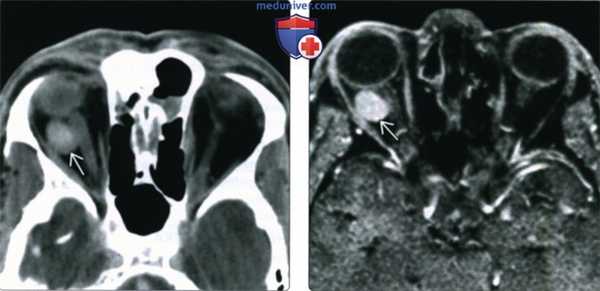

(Слева) У ребенка с периодически усиливающимся экзофтальмом при КТ с КУ в корональной проекции в верхнемедиальном квадранте переднего отдела глазницы определяется дольчатое образование от средней до низкой плотности, вызывающее смещение глазного яблока.

(Справа) При КТ с КУ в аксиальной проекции у этого же пациента в толще образования определяются множественные лакуны, содержащие жидкости различной плотности с отчетливыми уровнями. Более плотные длительно существующие продукты разложения крови оседают книзу.